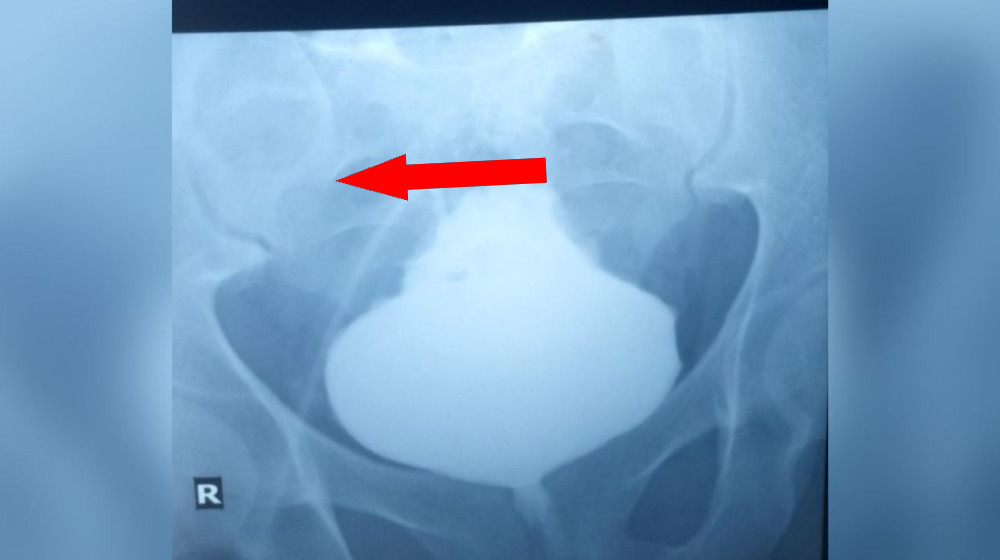

Чтобы понять причины симптомов, врачи направили пациента на радиологические исследования. В процессе исследования использовался контрастный препарат — рентгеноконтрастное вещество, введённое через брюшной катетер. Результаты показали, что дно мочевого пузыря было значительно расширено и имело необычную форму — заостренный, «вытянутый» верхний край. Такая форма напоминала ель, новогоднюю елку, что и дало основание назвать это состояние «ёлкаобразным мочевым пузырём».

«Это очень редкое и поразительное явление, которое показывает, насколько сильно может измениться форма мочевого пузыря при определённых условиях», — отмечают ведущие урологи и радиологи в исследованиях по редким патологиям.